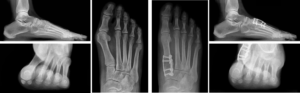

Lapiplasty® Case Examples